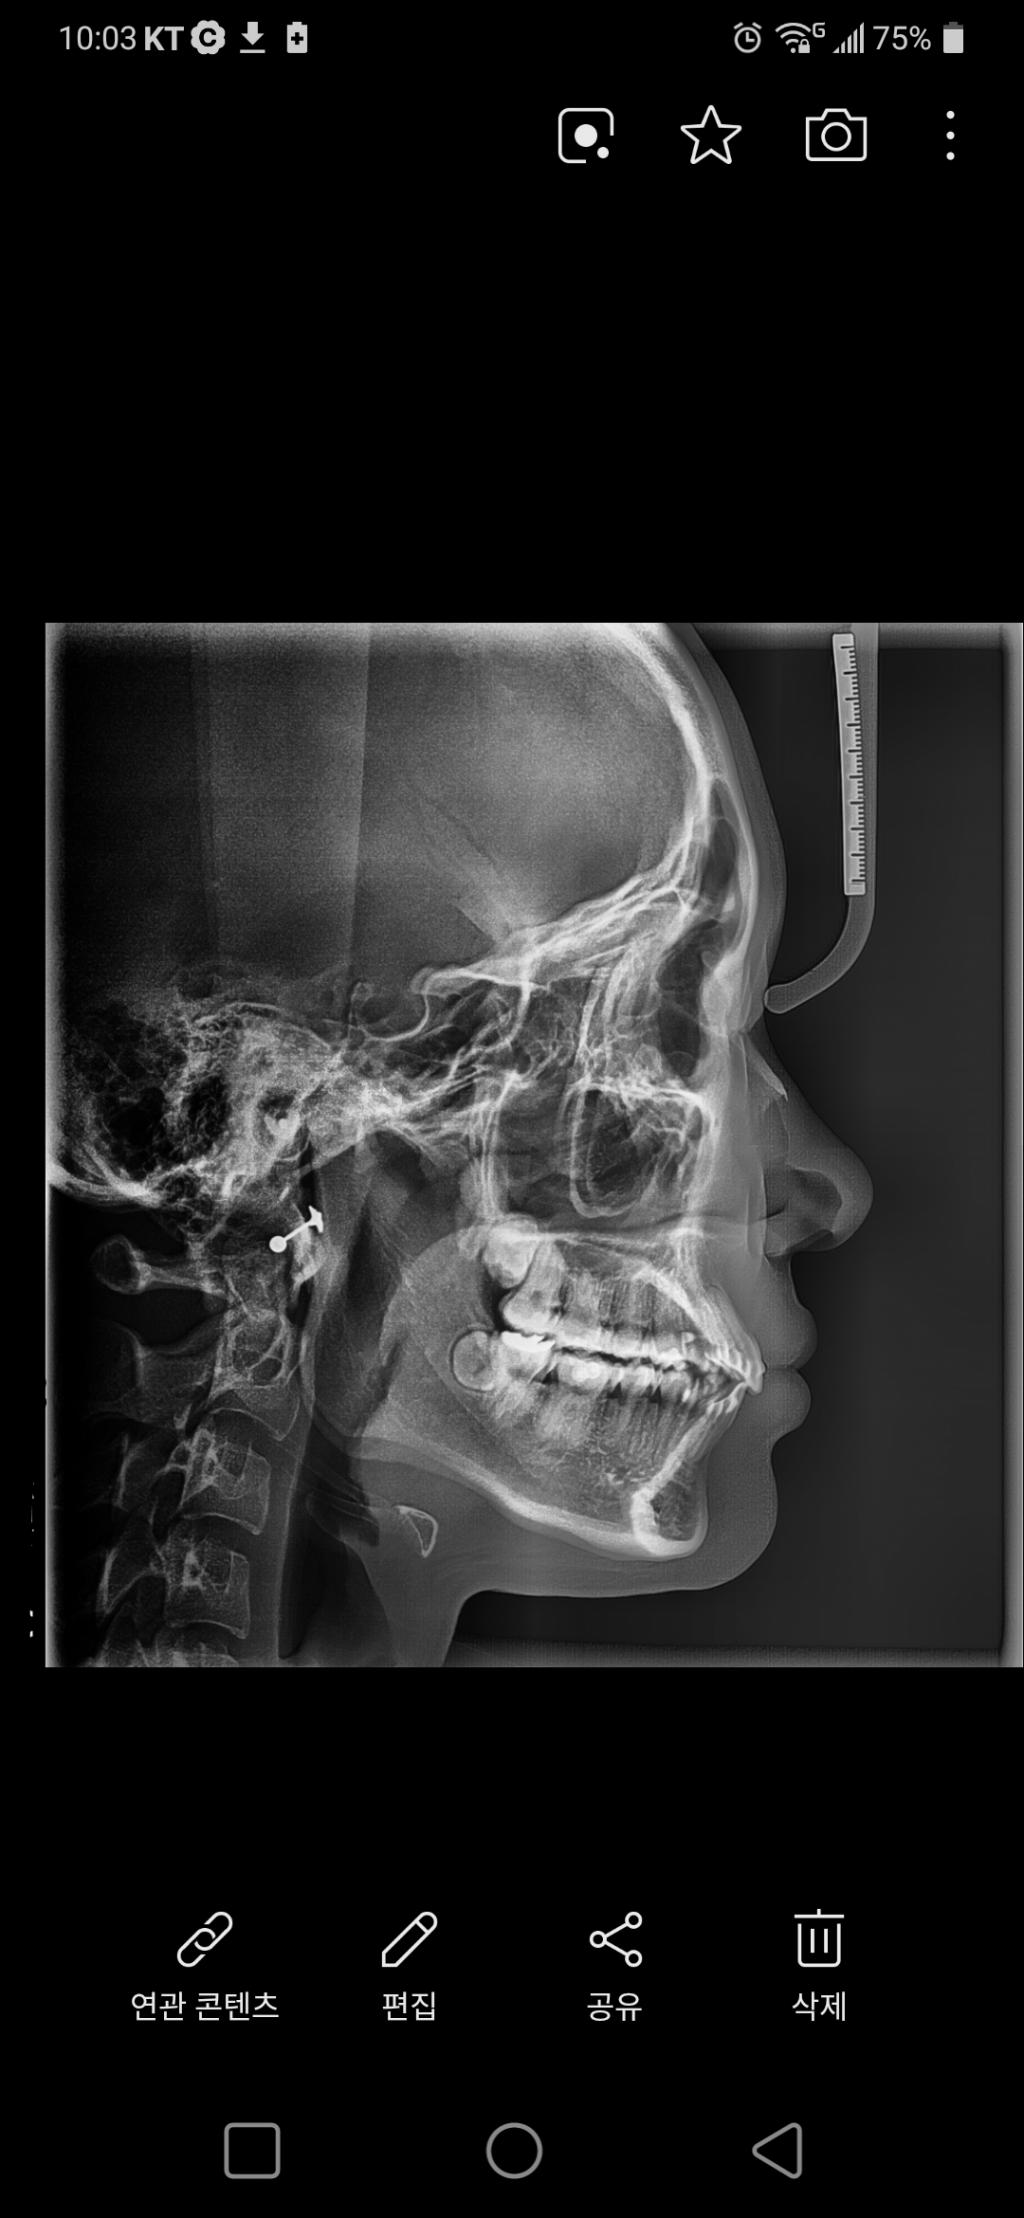

이 두사진의 차이가 왜 생긴걸까요?

아래가 교정후예요..안모가 더 나빠졌어요..이중턱도 생기고 턱이 두리뭉실해졌어요. 재교정하면 좋아질까요?